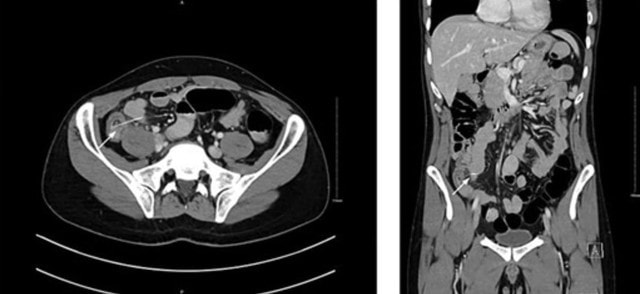

Các bác sĩ đã bối rối cho đến khi chụp CT phát hiện ra dị vật nhỏ có kích thước 3,7 cm, mà họ cho rằng đó là một chiếc xương vô tình nuốt phải từ bữa tối với thịt gà.

Họ đã yêu cầu phẫu thuật nội soi khẩn cấp để tìm hiểu thêm và phát hiện ra nguyên nhân: một chiếc tăm gỗ đã đâm thủng ruột, theo như Need To Know đưa tin .